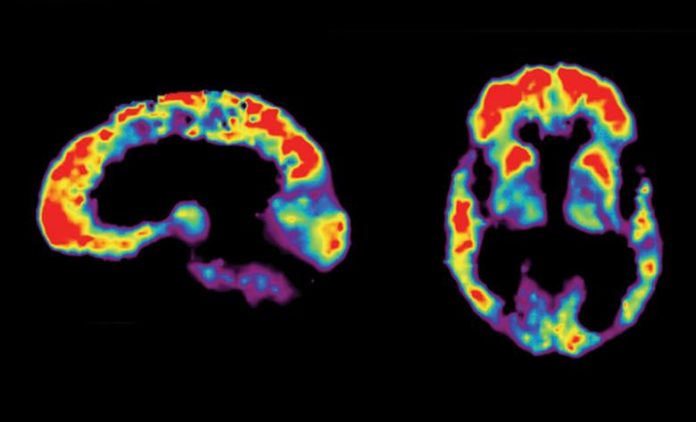

Utilizando técnicas espectroscópicas novedosas y convencionales, el equipo de Daggett observó las etapas individuales del desarrollo de los grupos beta amiloides, desde los monómeros hasta los oligómeros de seis y 12 proteínas hasta las placas, en líneas celulares neurales humanas.

Los investigadores confirmaron que los estadios oligoméricos eran más tóxicos para las neuronas, lo que concuerda con los informes clínicos de las placas beta amiloides en los cerebros de las personas que no tienen Alzheimer.

Los péptidos también protegieron a los animales de laboratorio del daño de oligómeros tóxicos. En muestras de tejido cerebral de ratones, el equipo observó una caída de hasta el 82% en los niveles de oligómero beta amiloide después del tratamiento con un péptido de hoja alfa sintético.

La administración de una hoja alfa sintética a ratones vivos provocó una caída del 40% en los niveles de oligómero beta amiloide después de 24 horas. En el gusano común de laboratorio Caenorhabditis elegans, otro modelo para la enfermedad de Alzheimer, el tratamiento con láminas alfa sintéticas retrasó el inicio de la parálisis inducida por beta amiloide. Además, los gusanos C. elegans mostraron signos de daño intestinal cuando se alimentaron con bacterias que expresan beta amiloide. Ese daño se inhibió cuando los científicos trataron por primera vez a las bacterias con sus hojas alfa sintéticas.